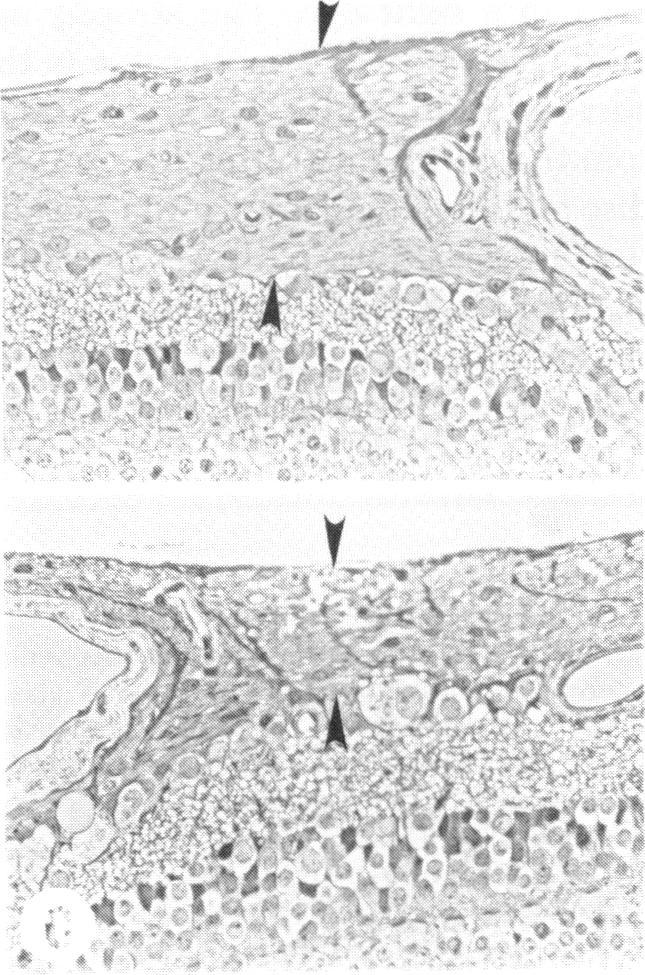

Examination of the retinal nerve fiber layer in the recognition of early glaucoma damage.

Trans Am Ophthalmol Soc. 1986;84:920-66.

Examination of the retinal nerve fiber layer in the recognition of early glaucoma damage.视网膜神经纤维层检查在早期青光眼损害识别中的应用